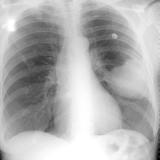

Mets

Album: Mets

Date: 02/18/2006

Size: 52 items

Views: 40060